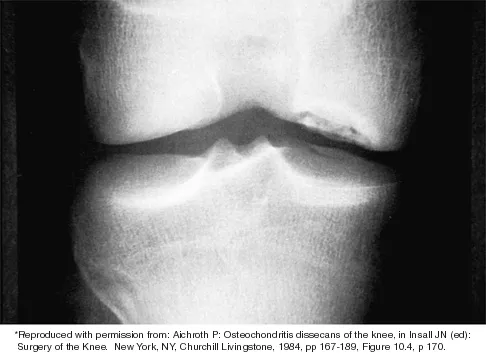

Which of the following primary prognostic factors best predicts the outcome of the knee lesion shown in Figure 22?

Explanation